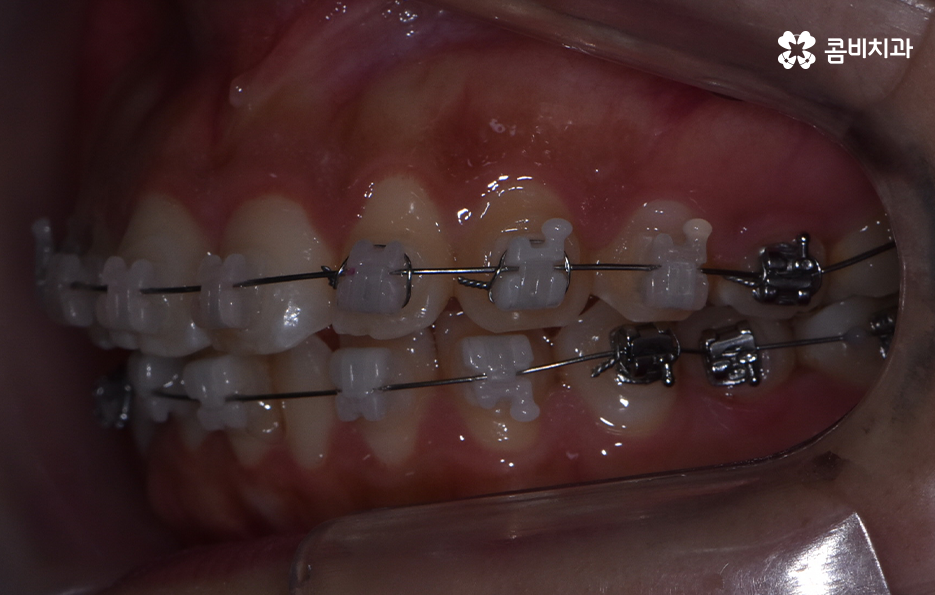

덧니는 윗니와 아랫니에 모두 있거나 앞니에 살짝 있는 수준의 덧니도 있으며 덧니가 심한 경우에는 개방교합으로 인해 입이 잘 다물어지지 않는 경우도 있기 때문에 덧니가 심한 정도에 따라서 치아교정의 계획은 세부적으로 달라질 수 있어요

덧니가 심하지 않은 경우에는 비발치로도 충분히 교정을 하는 경우도 있겠지만 덧니가 심한 경우에는 덧니 발치 교정을 통해서 치료가 진행되는 경우가 많이 있는데요. 그 이유는 치아교정의 원리를 생각하더라도 치아를 재배치하기 위해서는 기존의 치아가 움직일 공간이 필요한데 덧니는 치열이 이미 완성되고 있는 상태에서 치아가 나올 공간이 부족하여 덧니가 되는 경우가 많다는 점에서도 치아의 이동 공간을 확보하기 위한 발치가 필요할 수 있는 거예요